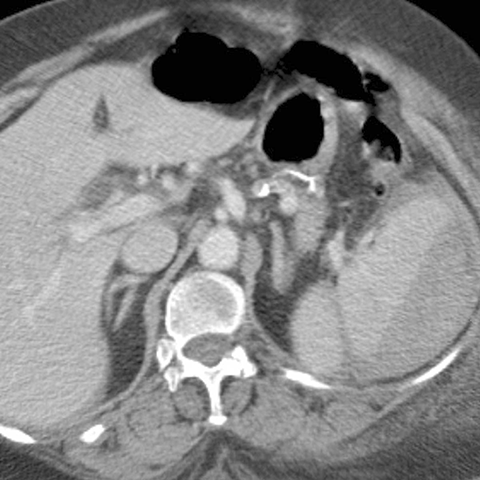

23-year-old male presents with blunt abdominal trauma after a motor vehicle accident [3 of 3]